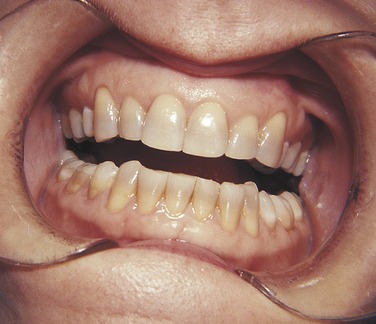

PLATE 15 Discoloration of teeth caused by tetracycline ingestion.